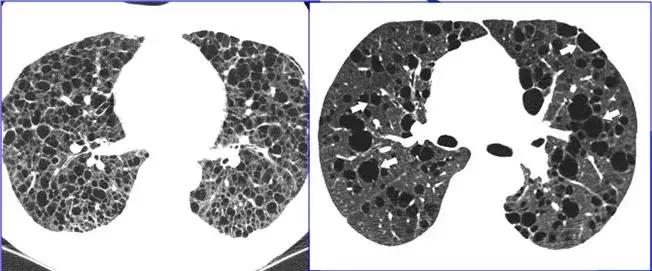

空腔病变

CT征象十:肺间质征与蜂窝肺

蜂窝肺表现为:两肺内大小数mm~数cm,壁菲薄的多发呈蜂窝状的透亮影,多见于肺间质纤维化病变的晚期。

肺间质纤维化晚期——两肺蜂窝影

两肺弥漫蜂窝影-肺淋巴管肌瘤病,均为女性